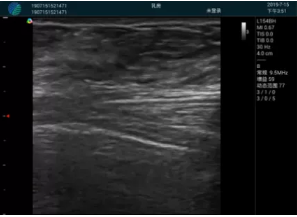

清晰顯示孕囊,通過軟件包計(jì)算孕齡7w+6d

M20實(shí)時(shí)引導(dǎo),術(shù)中清晰顯示孕囊被破壞和抽吸針的過程,清晰顯示吸引針

抽吸結(jié)束后縱切子宮,孕囊已被完全抽吸,未見明顯殘留

橫切子宮,發(fā)現(xiàn)右側(cè)宮腔靠近宮角處有少許脫模樣殘留

M20引導(dǎo)下,抽吸針找到右側(cè)宮角處再次清掃

二次抽吸后再次進(jìn)行超聲檢查,宮腔未見殘留,宮腔線清晰顯示